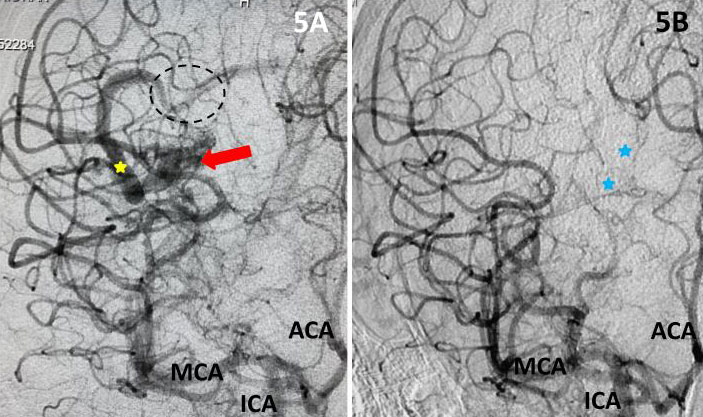

The patient was taken to the angio-suite where an angiogram confirmed a high flow, high pressure AVM fed primarily by the posterior cerebral artery with a small collateral from the middle cerebral artery (Fig 2 and 3). The AVM drained into a tortuous, partially occluded and stenotic single draining vein.

Fig 2. AP view, mid-arterial phase of a right internal carotid artery (ICA) injection. The large tortuous draining vein (yellow star) with the suggestion of clot (dotted circle) can be seen. AVM nidus (red arrow), MCA (middle cerebral artery, ACA (anterior cerebral artery).